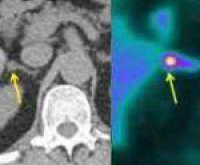

Исследования показали, что высокотехнологичное ПЭТ-КТ сканирование может обнаружить синдром Конна, который вызывает до пяти процентов от случаев гипертонии.

Синдром Конна трудно диагностировать, поскольку его вызывает доброкачественная опухоль или аденома в одном из надпочечников. Аденома продуцирует альдостерон, провоцируя гипертонию. Удаление опухоли или снижение уровня гормона излечивает высокое артериальное давление.

Ученые провели обследование 44 пациентов с помощью «позитронно-эмиссионной томографии в комбинации с рентгеновской компьютерной томографией». Исследователи разработали специальный радиоактивный индикатор 11C-metomidate, которые обнаруживает аденому. Тест занимает около 45 минут.